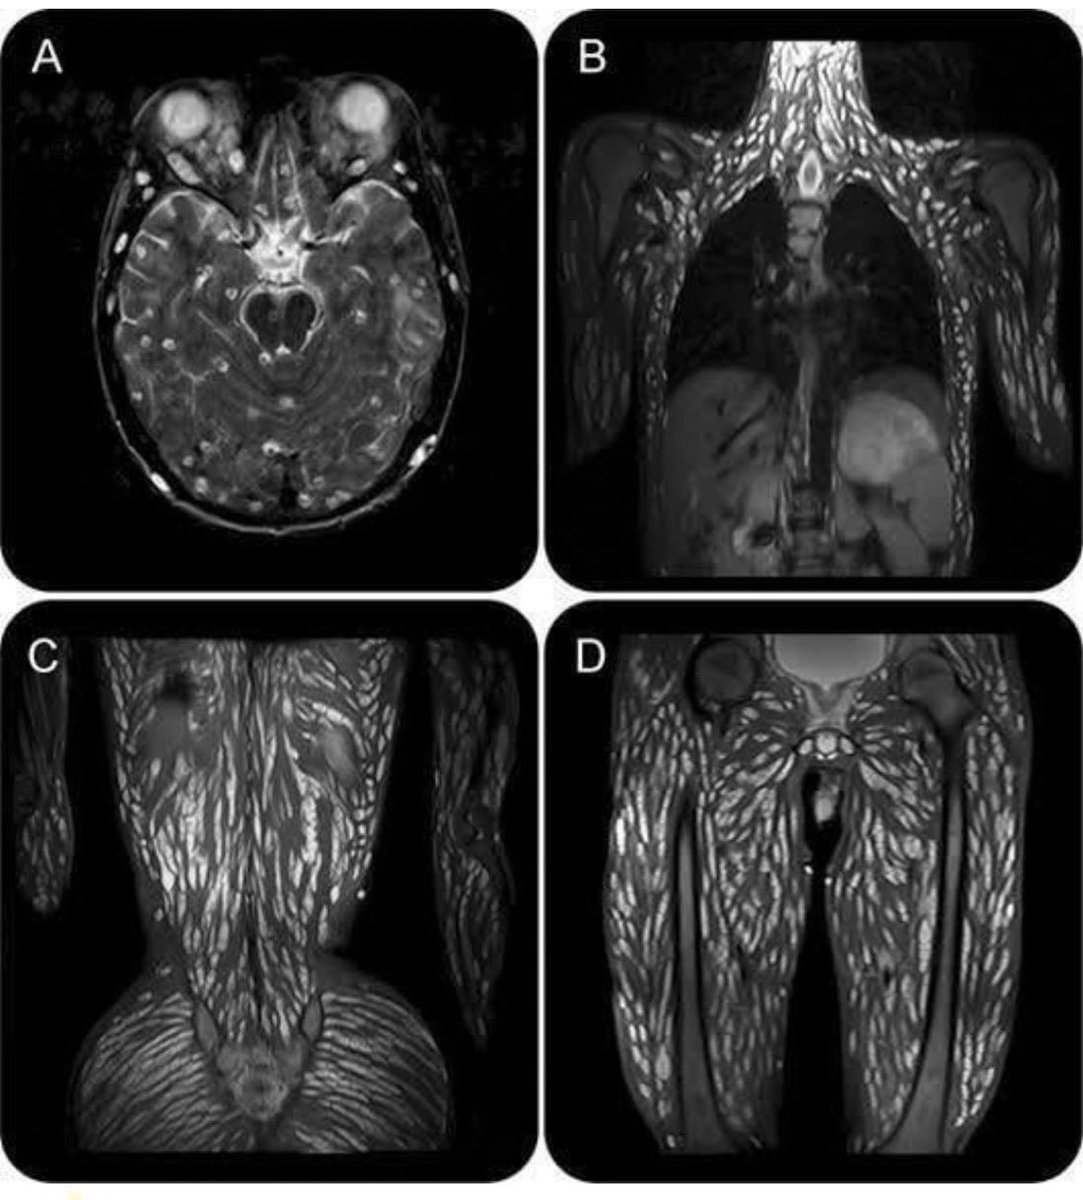

因食用未煮熟的猪肉而感染寄生虫的人。那些白色的东西是卵囊。 “MRI 显示脑实质、头皮、眼外肌、颈部、胸壁、腹壁、椎旁、臀部、骨盆和四肢肌肉中有不同阶段的多个囊肿(图)” https://t.co/3AI6jL0Fti